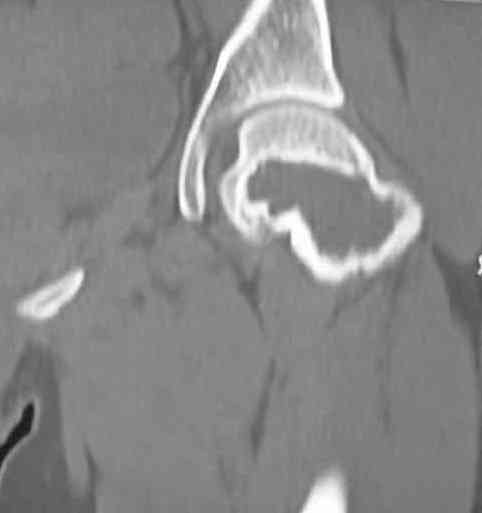

Больная Л., 23 года. Из анамнеза:со слов больной в 2006 г. появились боли правой н/конечности, обратилась поместу жительства к хирургу, было выполнена МРТ поясничного отдела позвоночника,назначено физиолечение. Через 2 месяца боли прекратились, через 4 месяца рецидив болевого синдрома. С 2006 – 2010 проводилось консервативное лечение по поводу остеохондроза поясничного отдела позвоночника. В октябре 2010 г. боли усилились. Выполнены Ro и КТ правого тазобедренного сустава, выявлен очаг патологической перестройки. Была направлена на консультацию в УНИИТО. В УНИИТО виюне 2011 г. поставлен дифференциальный диагноз между фибромой, солитарной костнойкистой и гигантоклеточной опухолью.

Клиника и течение заболевания похожи на однокамерную кисту. Больная молодая, желательно сохранить собственную головку. Надо спешить с операцией, иначе скоро произойдет перелом через тонкую стенку. Во время операции внутри будет пустота и небольшое количество жидкой крови.

Из всех перечисленных методов подходит вариант пластики аутокостью и усиление (арматура) шурупами. Основная задача сохранить интактную медиальную стенку и латеральный кортекс. Доступ передне-латеральный, но надо работать спереди шейки через небольшое окно в 10-15 мм. Фиксацию надо проводить между медиальной тонкой стенкой головки и латеральным кортексом. Каннюлированные шурупы 6.5 мм очень грубые и могут разрушить остаток стенки. Фиксировать надо кортикальными шурупами 3.5 мм, которые создадут мостик и арматуру в шейке. Провести по периметру шейки 4, и в центре пару шурупов. Во время операции и при манипуляции соблюдать осторожность, в любой момент может наступить стресс перелом. Заранее надо заказывать длинные шурупы!